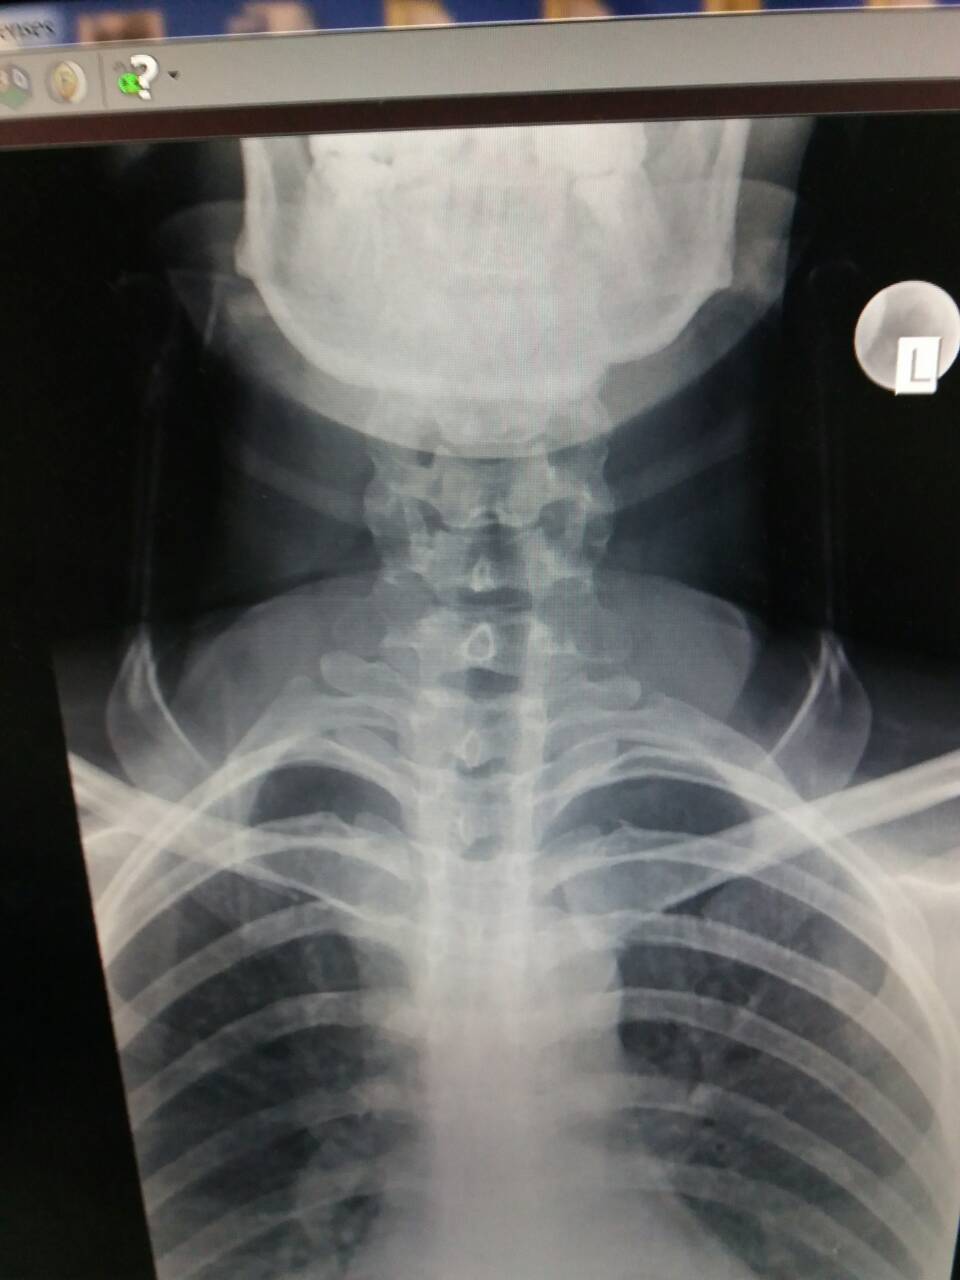

Fractur dislocation vert.C2

Выписка из предыдущей больницы от 5 февраля, где перелом позвонка С2 диагностировали (только 5 февраля, только на 2-й КТ, на первичных рентгене и кт не видели)

Fractura vertebrae cervicalis secundae – II;

x-ray.jpg

x-ray-1.jpg

cervical spine-5 febr-1.jpg